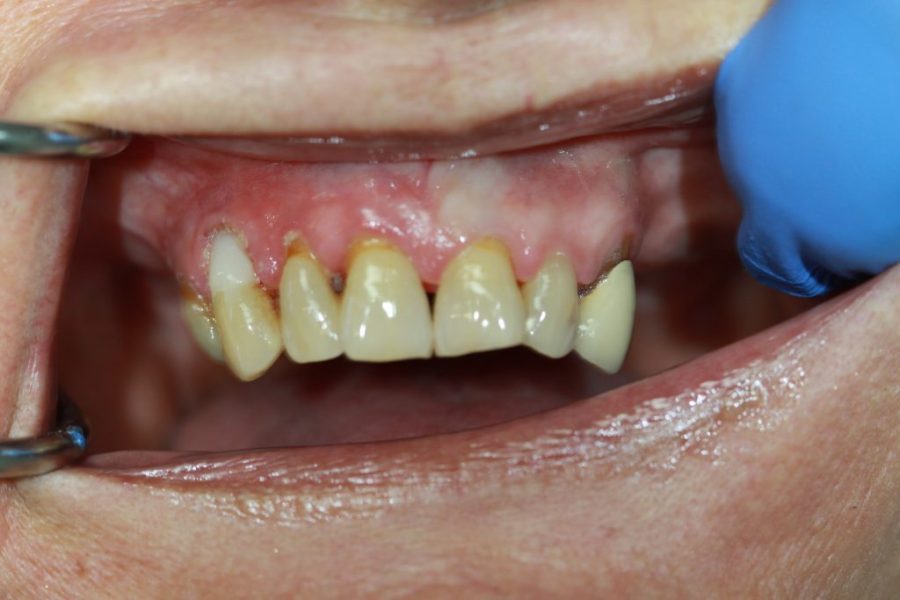

Rose’s Story: A Stunning Smile with Composite Veneers

Rose wanted to tidy up her front teeth and opted for composite veneers. After just 60 minutes, her smile was transformed. Rose couldn’t be happier with the results and graciously allowed us to share her story.